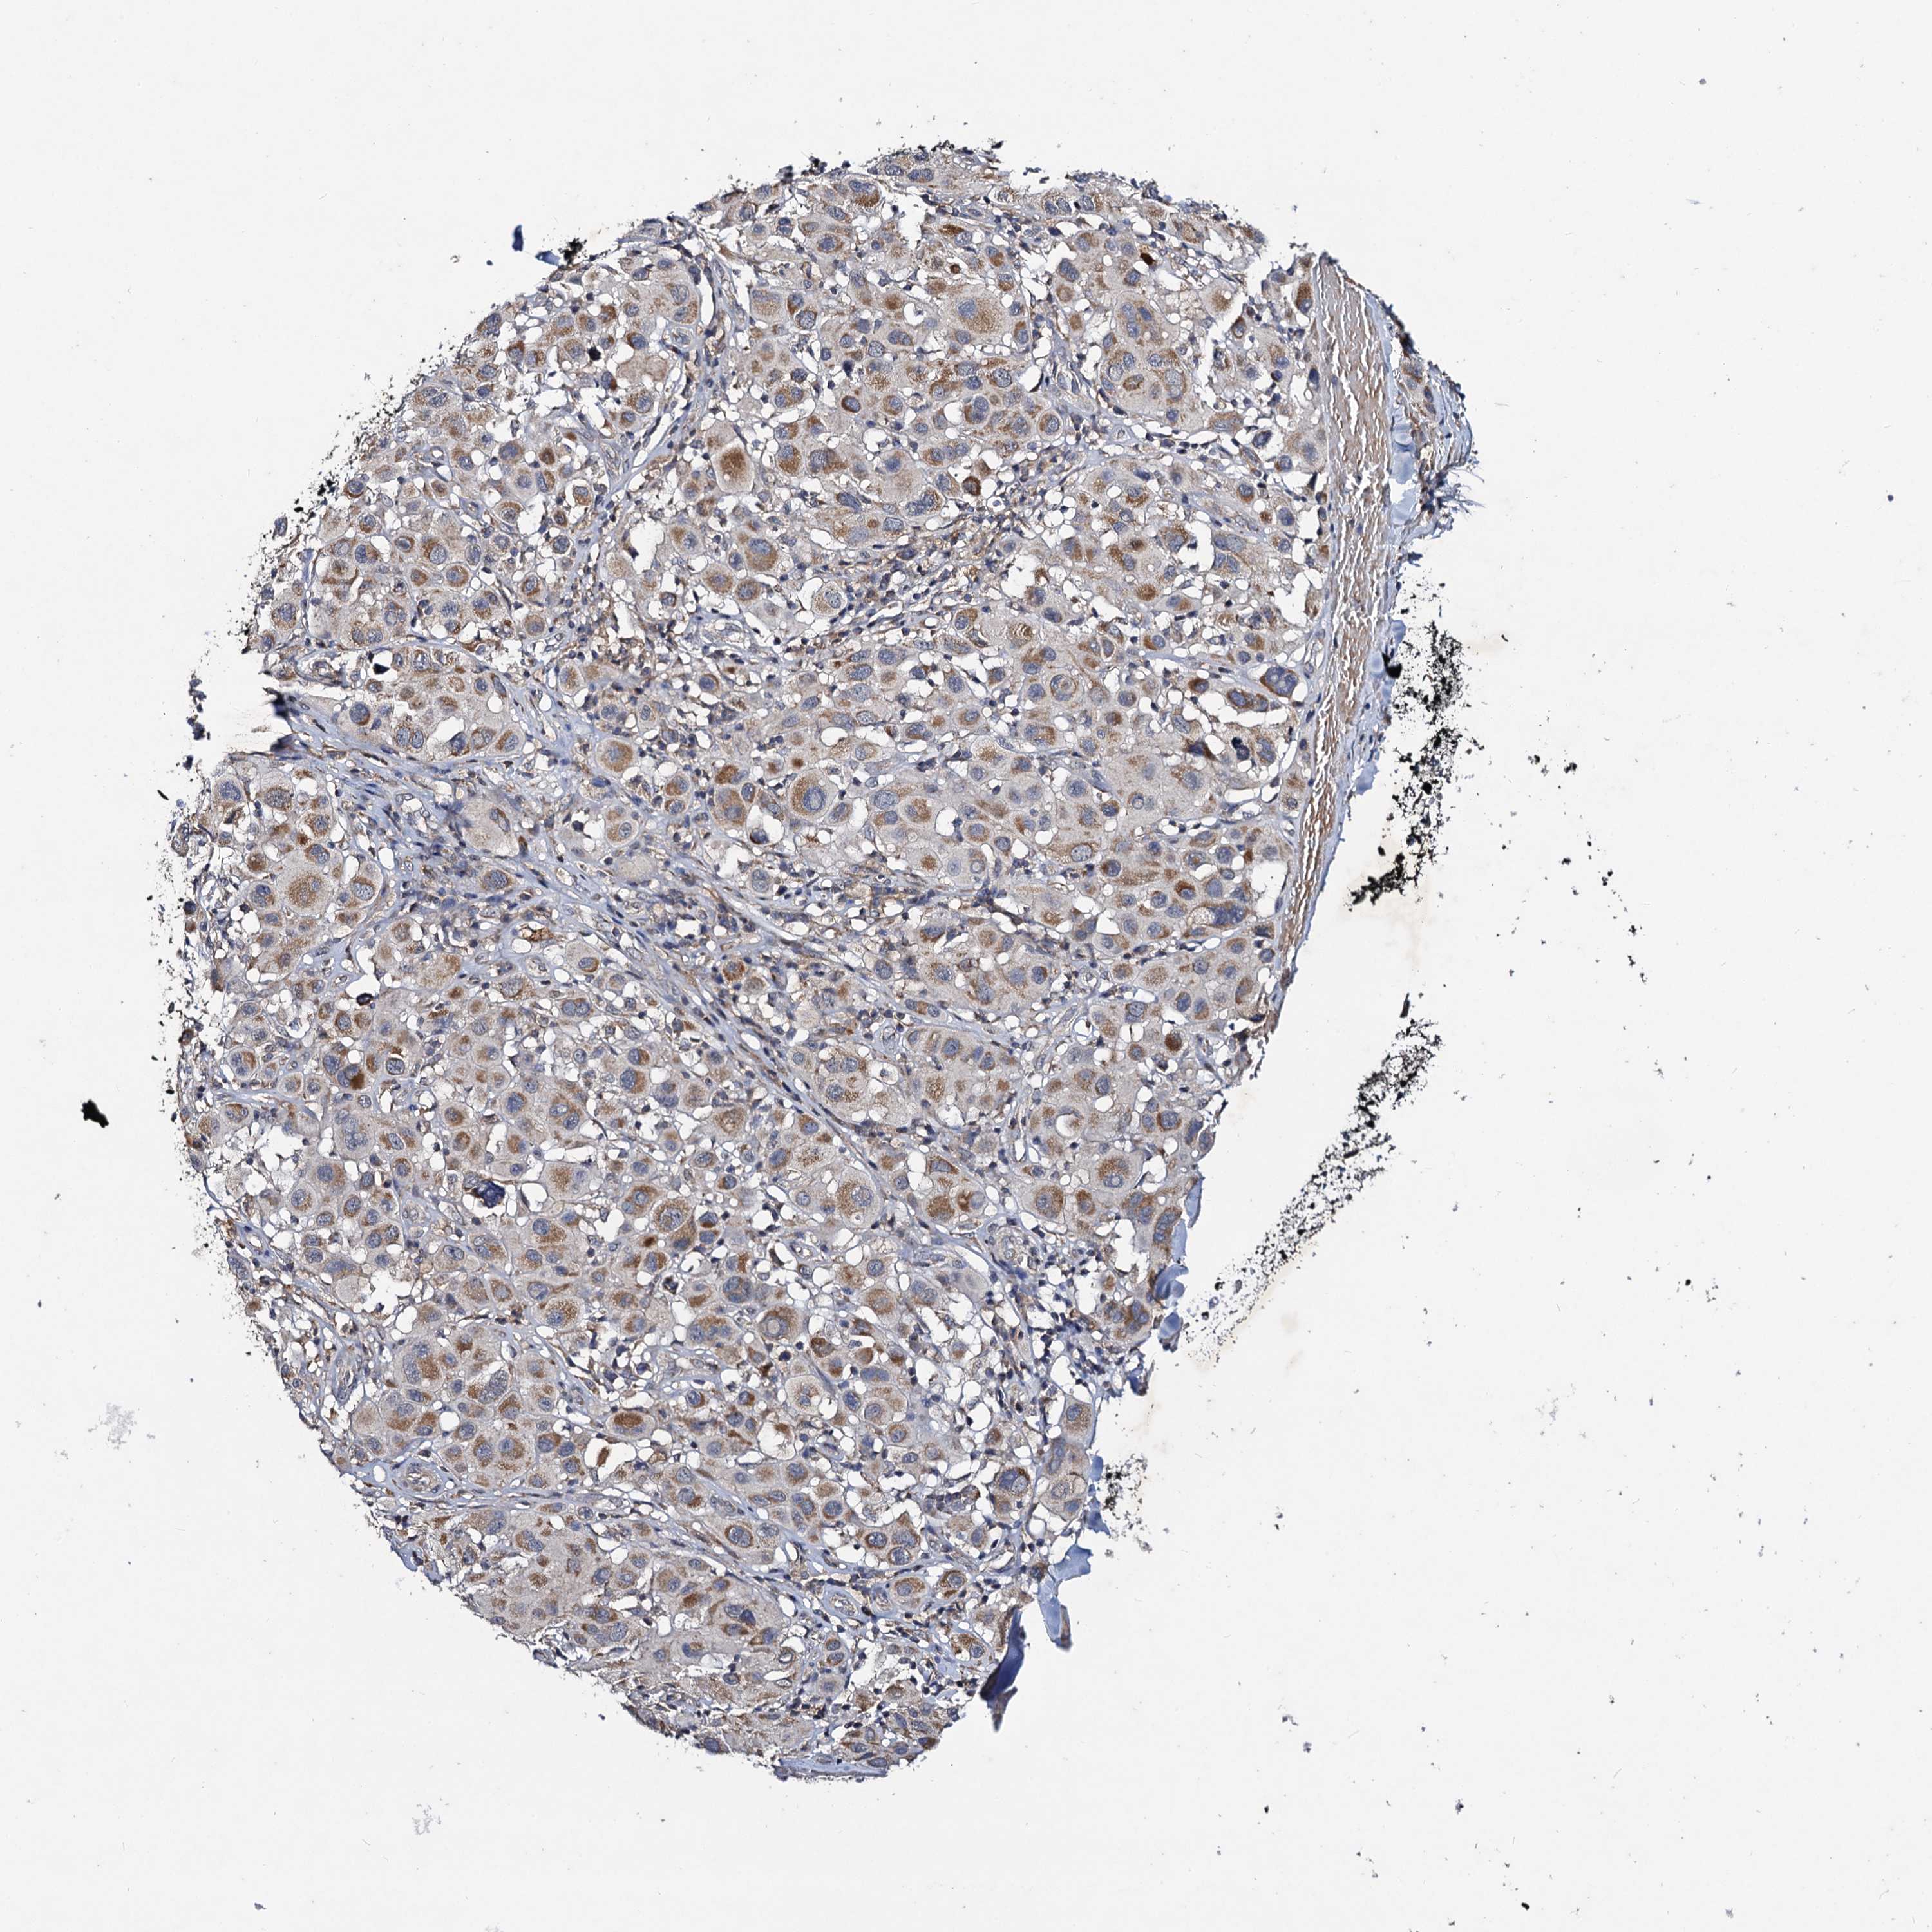

MELANOMA - Protein expressioni

A mouse-over function shows sample information and annotation data. Click on an image to view it in a full screen mode. Samples can be filtered based on level of antibody staining by selecting one or several of the following categories: high, medium, low and not detected. The assay and annotation is described here.

Note that samples used for immunohistochemistry by the Human Protein Atlas do not correspond to samples in the TCGA dataset.

Antibody stainingi

Antibody staining in the annotated cell types in the current human tissue is reported as not detected, low, medium, or high, based on conventional immunohistochemistry profiling in selected tissues. This score is based on the combination of the staining intensity and fraction of stained cells.

Each image is clickable and will lead to virtual microscopy that enables deeper exploration of all samples and also displays staining intensity scores, fraction scores and subcellular localization as well as patient and tissue information for each sample.

Antibody HPA040978

Staining

High

Medium

Low

Not detected

Intensity

Strong

Moderate

Weak

Negative

Quantity

>75%

75%-25%

<25%

None

Location

Nuclear

Cytoplasmic/membranous

Cytoplasmic/membranous,nuclear

Malignant melanoma, NOS

Malignant melanoma, Metastatic site